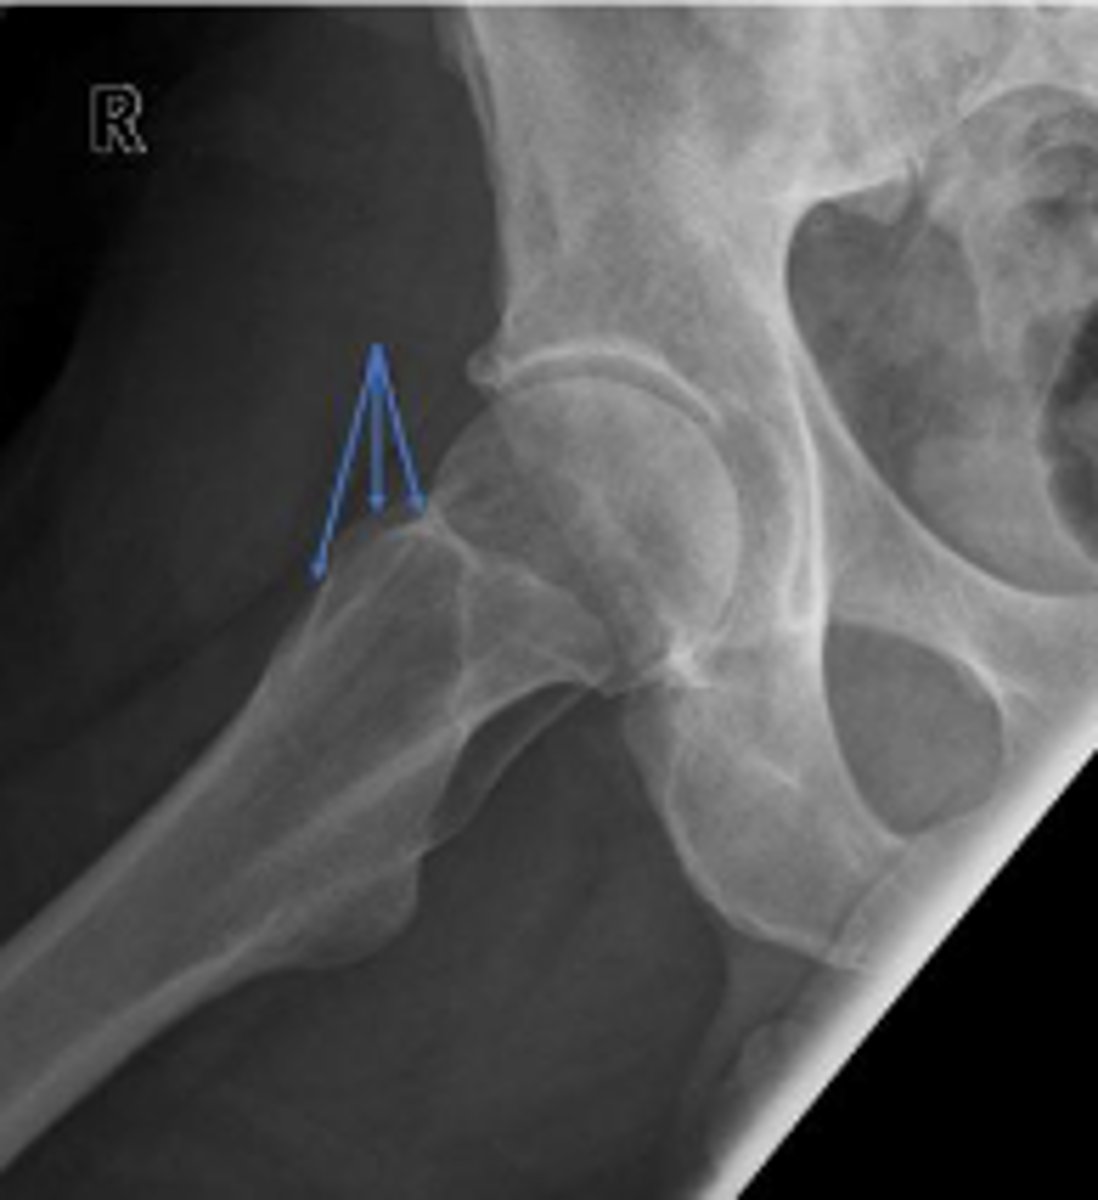

Posterior hip dislocation

What is most significant radiographic finding?

Shenton's line

What is the name of the assessment?

From the undersurface of the femoral neck

continued to the inferior aspect of the superior

pubic ramus

What are the osseous land marks for this assessment?

Hip dislocation, fracture

Name 2 conditions that may result in an abnormal assessment?